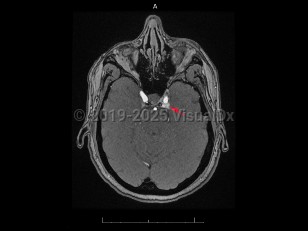

Imaging Studies image of Carotid-cavernous fistula - imageId=7872355. Click to open in gallery.  caption: '<span>Axial post-contrast MR image demonstrates abnormal opacification of the left cavernous sinus, consistent with  carotid-cavernous fistula.</span>'

Axial post-contrast MR image demonstrates abnormal opacification of the left cavernous sinus, consistent with carotid-cavernous fistula.